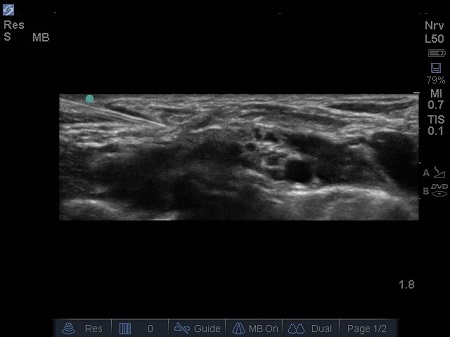

- The probe should be angled/tilted till an optimal image is obtained where we can clearly identify these four structures: the subclavian artery, the first rib, the pleura and the brachial plexus.

- The first structure to locate is the round pulsating hypoechoic subclavian artery (A), lying on top of the hyperechoic first rib (R). Use Doppler to assess for vessels. See Fig. 2.

Fig. 3. Sonoanatomy of infant supraclavicular region. A – Subclavian artery. B – brachial plexus, P – pleura, R – first rib, V – subclavian vein

- Lateral and above the artery sit a bundle of round hypoechoic circles (“bunch of grapes” or “cluster of bubbles”) – the brachial plexus, at this level, the plexus will be configured as trunks and/or divisions.

- It may be possible to identify the hypoechoic nodules surrounded by a hyper-reflective fascial sheath.